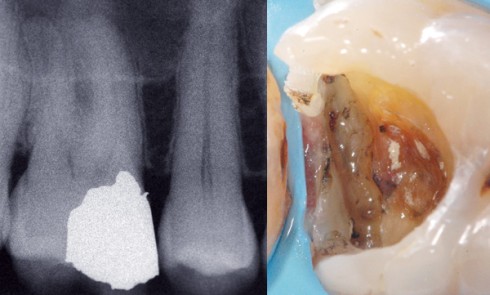

Article réservé à nos abonnés Reconstitution corono-radiculaire fibro-architecturée

La solution exposée dans cet article découle d’une analyse critique des concepts actuels, de l’exploitation de nos connaissances en matière...